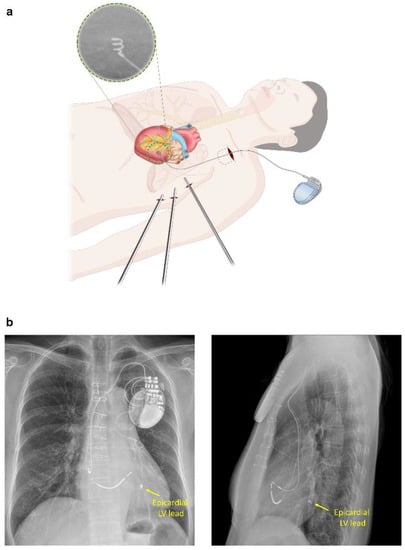

2.2. Epicardial LV Lead Implantation for CRT